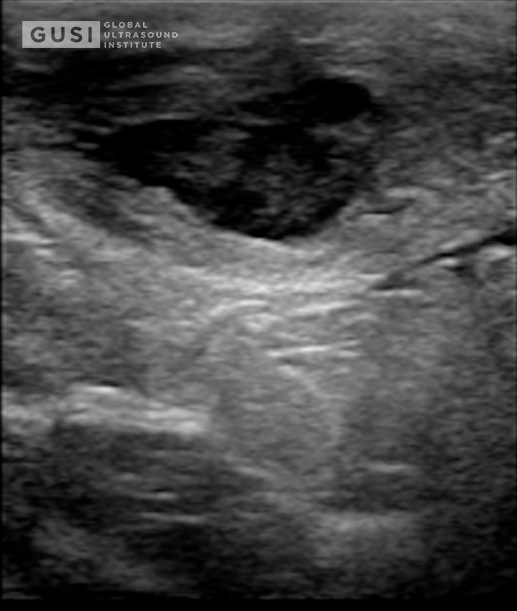

History of Present Illness:

A 28-year-old female with a past medical history of bilateral breast mammoplasty and obesity presents to the Emergency Department with acute onset right breast tenderness, erythema, and edema. She also noted a low-grade fever of 38.5 degrees Celsius accompanying these symptoms. The patient underwent bilateral breast mammoplasty 12 months ago and reported a previous episode, approximately 9 months post-surgery, of a small right breast lesion causing discomfort. This lesion fluctuated in size but resolved without intervention. This time, however, the symptoms were more pronounced, with prominent tenderness, warmth, and redness. There were no overlying skin changes, nipple discharge, or recent trauma to correlate.

Physical Examination of Right Breast:

-

Tenderness: Prominent tenderness on palpation around the developing abscess at 2 o’clock with associated palpable fluctuance.

-

Erythema and Edema: Observable redness and swelling on the outer quadrant mentioned above.

-

Calor (Warmth): Increased warmth over the affected breast area.

-

Rubor (Redness): Noticeable redness around the involved area.

-

No Nipple Discharge: No spontaneous nipple discharge.

-

No Overlying Skin Changes: Absence of skin changes over the right breast.

Management:

An ultrasound-guided needle aspiration successfully drained 20 mL of sanguinopurulent material, which was sent for culture. The patient experienced immediate relief and was discharged home with a prescription for a 10-day course of oral amoxicillin-clavulanate (875-125 mg). She received a recommendation for close follow-up with her plastic surgeon for further interventions.

Microbiological Findings:

The initial Gram stain revealed Gram-positive rods, and 5 days later, laboratory data yielded pansensitive growth of Cutibacterium (Propionibacterium) avidum. The patient completed the antibiotic course and scheduled ambulatorial surgical intervention of an epidermoid cyst.